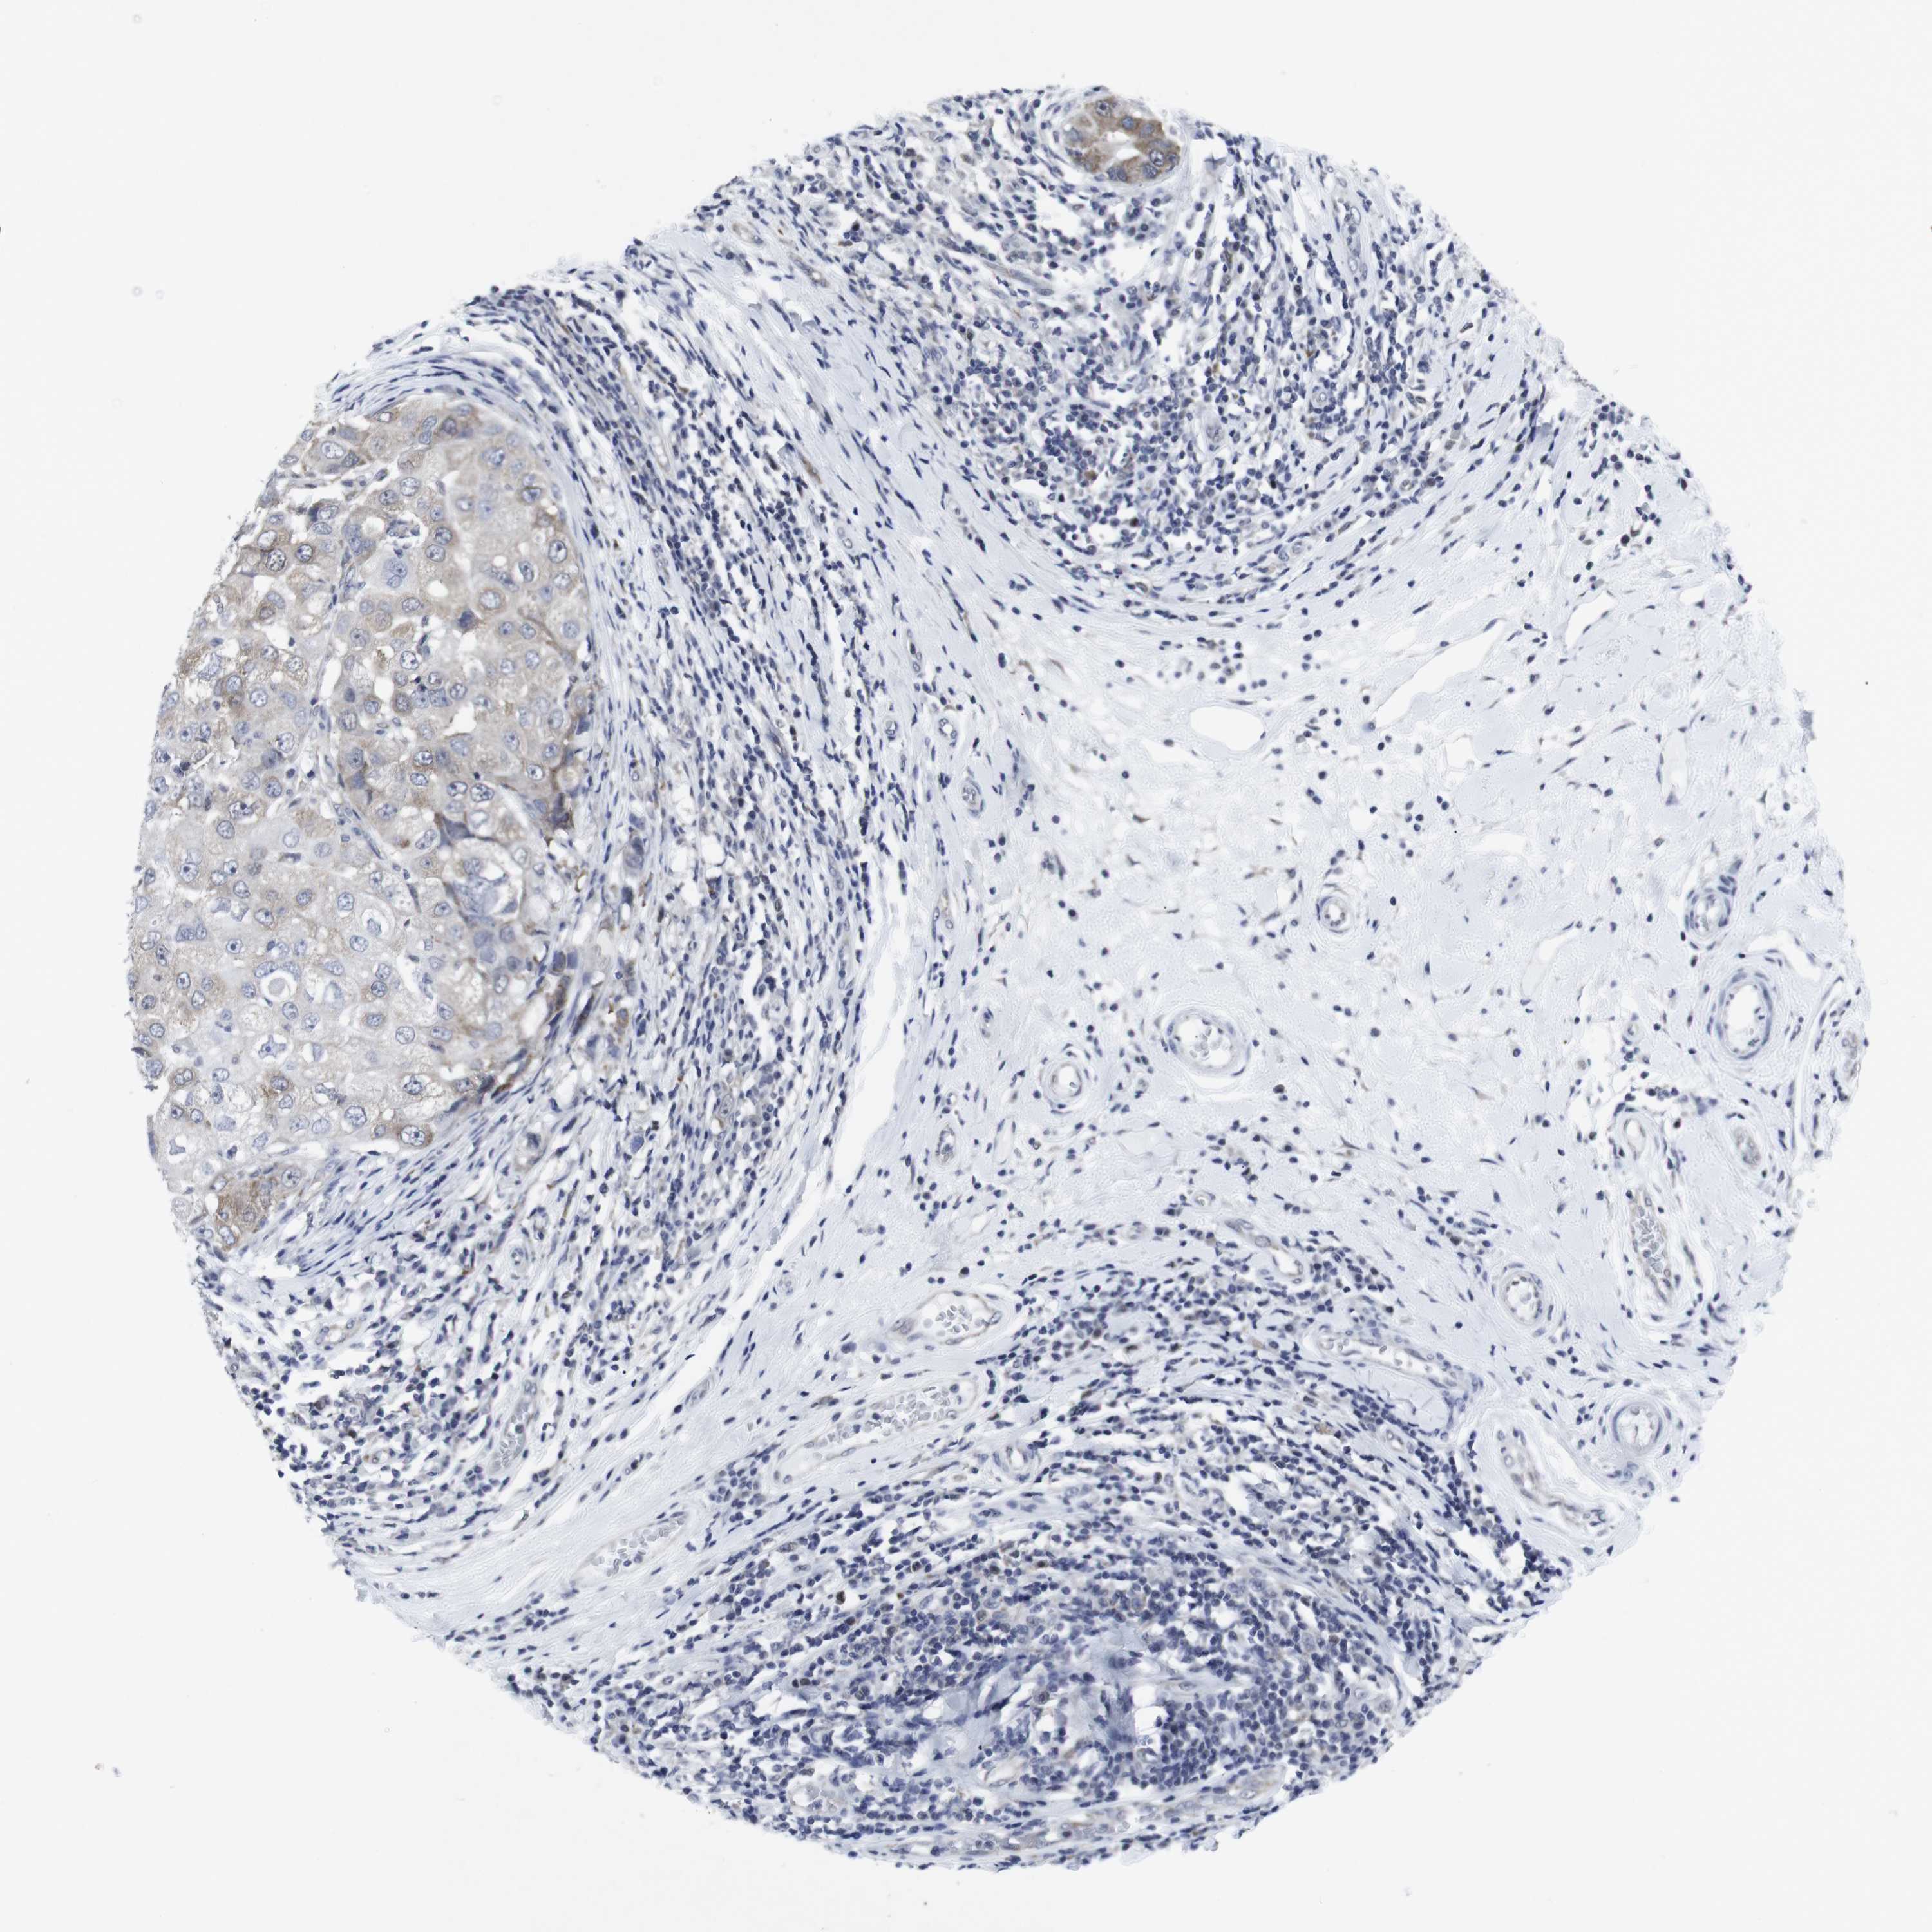

CANCER BREAST CANCER Show tissue menu

BRCA TCGA BRCA VALIDATION PROTEIN EXPRESSION

ANTIBODIES

AND

VALIDATION